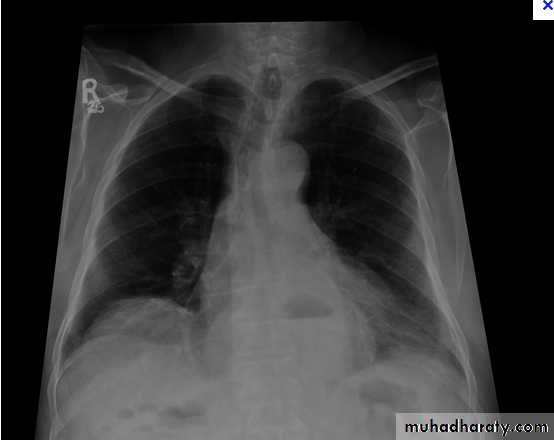

Right lower lobe consolidation - PA. Dense opacification in the right lower zone with effacement of the outline of the right hemidiaphragm.

• Right lower lobe consolidation - Lat.

• The density lies posterior to fthe oblique issure- the position of the lower lobe.